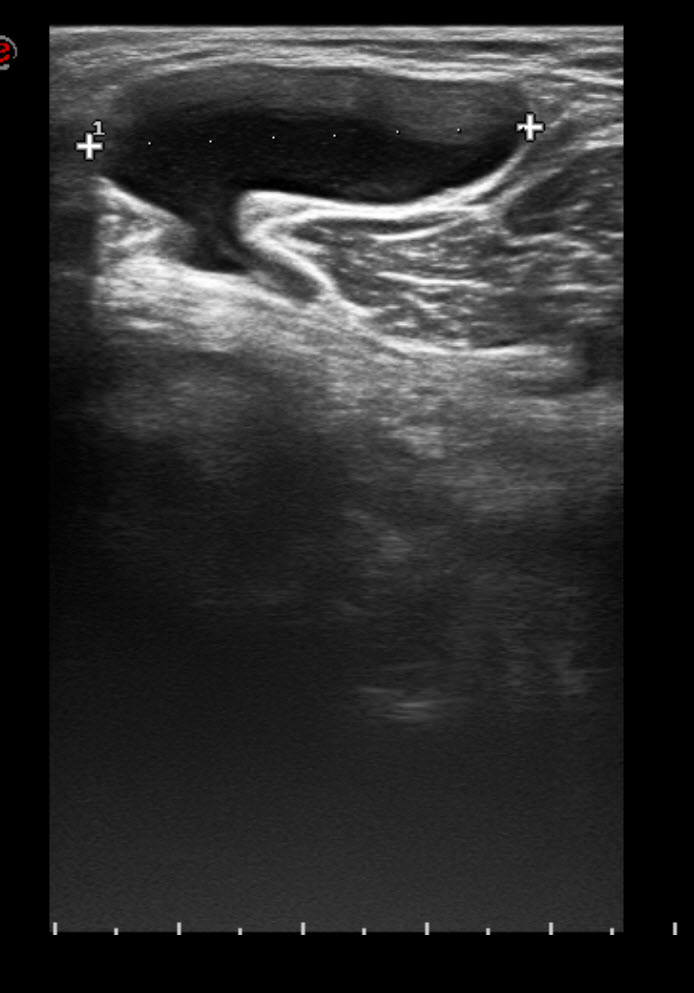

From sportdoctorlondon.com

Understanding Baker's Cyst on Ultrasound Causes and Symptoms Baker Cyst Knee X Ray Baker cysts are enlarged bursae in the popliteal fossa. They grow after something damages your knee joint or. They present as swelling in the popliteal. Citation, doi, disclosures and article data. The ability to detect baker cysts is near 100%, but ultrasound lacks the specificity to differentiate baker cysts from meniscal cysts or. They are filled with synovial fluid and. Baker Cyst Knee X Ray.